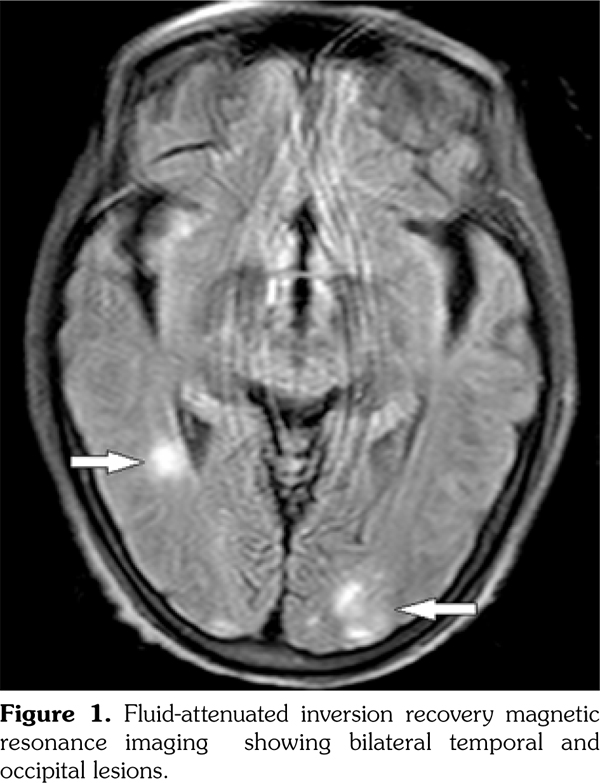

Posterior reversible encephalopathy syndrome (PRES) is known as reversible posterior leukoencephalopathy syndrome, primarily portrayed in 1996.(1) It is characterized by headache, vomiting, seizure, confusion, and visual disturbance. The brain magnetic resonance imaging is the diagnostic gold standard showing edema in the white matter of bilateral temporal, parietal, and occipital lobes for neuroradiologic characteristics, totally reversible.(2) To our knowledge, this is the first report of an elderly female patient of PRES complicated with systemic lupus erythematosus (SLE), Sjögren syndrome (SS), and primary biliary cirrhosis (PBC).

A 65-year-old female patient was admitted because of upper extremity shaking and lower extremity weakness for one day, fatigue, and anorexia for more than two months. She was firstly suspected of Parkinsonian syndrome. Levodopa and benserazide hydrochloride tablets were administered. However, her condition deteriorated aggressively, and it was hard for her to walk. Meanwhile, there were no complaints of rash, oral ulcer, baldness, arthritis, or photosensitivity. She denied headache, dizziness, vomiting, confusion, or double vision. Interestingly, she suffered from dry mouth and dry eyes for several months. She had never smoked or consumed alcohol, or received any suspected drugs. Physical examination was significant for fractured teeth and decreased myodynamia with 4/5 strength of upper extremity and 2/5 strength of lower extremity symmetrically. Laboratory tests revealed elevation of the 24-hour urine protein (1.20 g), positive autoantibodies (antinuclear antibody, anti- Smith, anti-double stranded deoxyribonucleic acid antibody) and decreased complement. SLE was diagnosed.(3) The positive tests of anti-Sjögren syndrome A antibody and Schirmer test, ocular staining score (>3) combined with clinical symptoms supported the diagnosis of SS,(4) but the patient refused labial salivary gland biopsy. Furthermore, PBC was diagnosed according to her raised alkaline phosphatase and positive serum anti-mitochondrial antibodies, excluding other causes of cholestasis. However, she rejected liver biopsy. Magnetic resonance imaging of the brain revealed symmetrically patchy lesion involving predominantly the subcortical white matter of the bilateral temporal and occipital (Figure 1). Therefore, she was ultimately diagnosed with PRES, SLE, SS, and PBC. Treatment was initiated immediately, including methylprednisolone 80 mg once a day, cyclophosphamide 400 mg∞3 days, plasmapheresis, and hypotensor. Several days later, her clinical symptoms improved greatly. Repeated magnetic resonance imaging was performed two months later, showing that the lesion had almost disappeared. Urinary protein proved to be 0.06 g/24 hour in follow-up. A written informed consent was obtained from the patient.